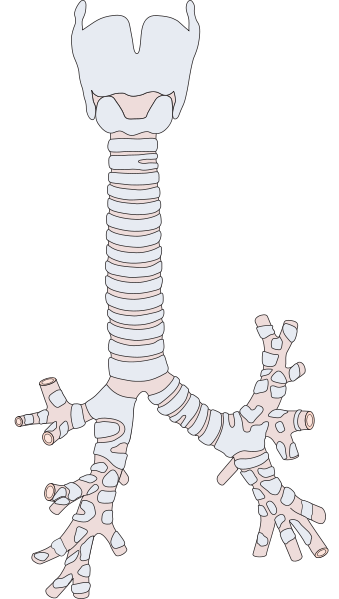

Le tonsille sono organi linfoghiandolari presenti nel cavo orale e svolgono una funzione di protezione dell’apparato respiratorio dai microrganismi presenti nell’aria.

Sono divise in quattro grandi categorie: tonsille faringee (adenoidi), tubariche, palatine e linguali.